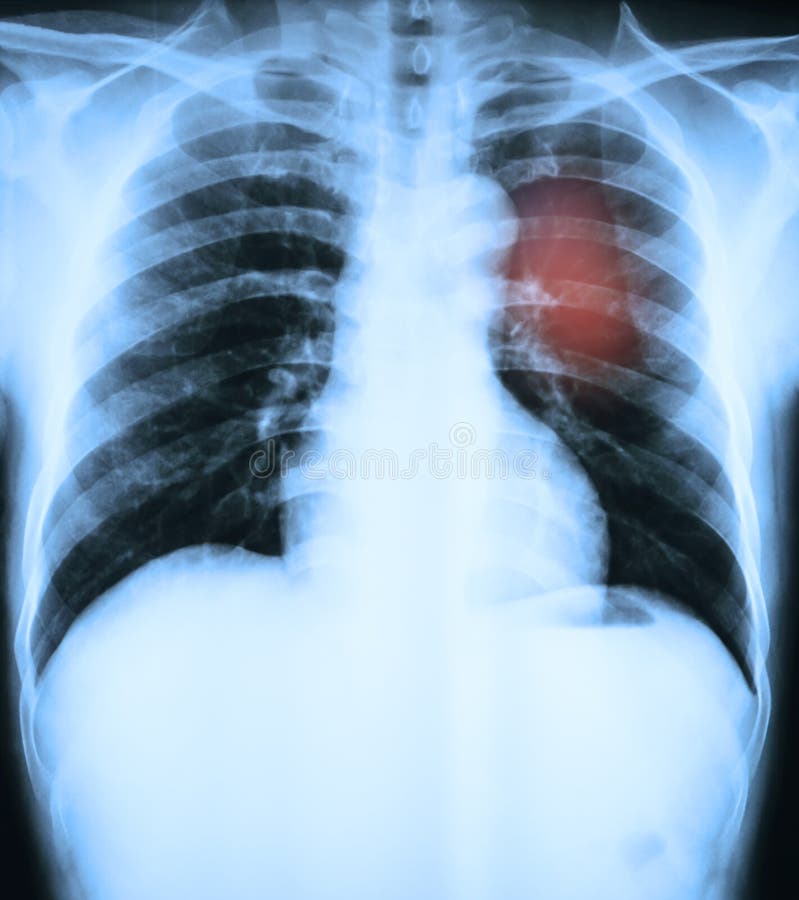

Здоровый образ жизни: Влияние курения

Раздел: Моменты озарения